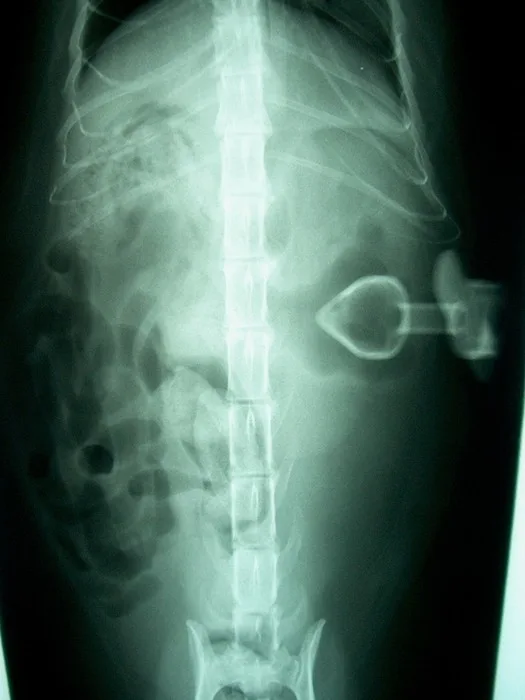

• Figures 5a & 5b. Lateral and ventrodorsal radiographs of low-form gastrostomy tube after infusion of 10 ml of iohexol. The tube is outside the abdominal wall, and contrast is dissecting subcutaneously. (Courtesy of Dr. Eric Ferrell, University of Florida)